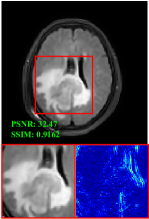

4.3 Qualitative results

Figure 5 provides the qualitative comparison of the various methods on the four datasets at a scale of 4. The top, second, third, and bottom rows are the SR results under the FastMRI, clinical brain, clinical tumor and clinical pelvic datasets, respectively. The red boxes indicate the zoom-in region of complicated anatomical structures along with their corresponding error maps. Note that the brighter textures in the error maps, the lower the quality of the reconstructed images. As can be seen, compared to methods based on Transformers and CNNs, diffusion-based methods like DisC-Diff and DiffMSR (Ours) are capable of reconstructing high-realistic images with promising reconstruction metric scores (PSNR and SSIM). Nevertheless, while DisC-Diff can reconstruct high-precision MR images, it does not preserve the structure present in the original HR images, introducing some additional information that can affect medical diagnosis. In contrast, our method combines DM and PLWformer, which can preserve the original image’s structure while restoring high-frequency information.

9 More Visual Comparisons

In this section, we present more visual qualitative comparisons. Figures 8, 9, 10, and 11 show the reconstruction results of each method in FastMRI, clinical brain, clinical tumor, and clinical pelvic, respectively. As can be seen, although DisC-Diff can reconstruct MR images with high-frequency information, it fails to preserve the structure and content of the original Target HR image effectively, resulting in image distortion. In contrast, our proposed DiffMSR can restore high-frequency information while preserving the structure of the original HR image, indicating the effectiveness of the joint use of DM and PLWformer.